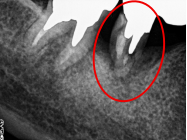

右下奥の歯が、グラグラして噛むと痛い。

治療内容

歯根の周りの骨が全く無い状態でしたので、保存することができず抜歯しました。3本歯がないところに2本インプラントを埋入しました。

Before

※赤丸を抜歯しました。

After